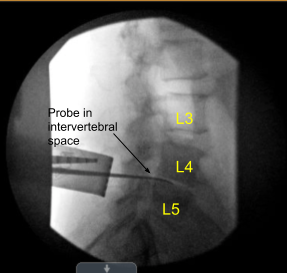

All the bony prominences were well padded. Spinal needle was used to mark the L4-5 intervertebral disc space. The lower back was prepped and draped aseptically in the usual fashion. Preop antibiotic in the form of 900mg of clindamycin was given. Time-out was called.

A fluoro was brought in and Woodson was put under the lamina of L4 and x-ray was taken to confirm our level. Once the level was confirmed, laminotomy of the left inferior L4 and superior laminotomy of left L5 was performed with the use of high-speed drill.